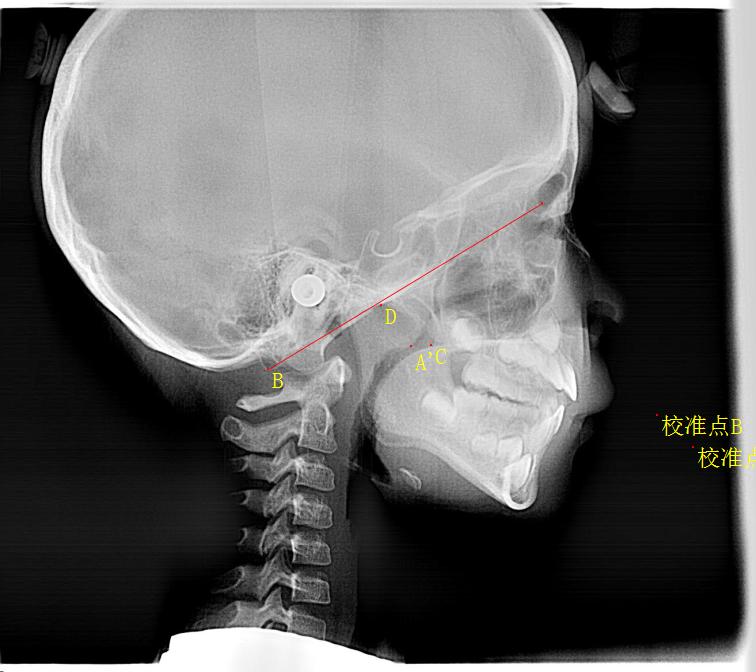

NO.1平时在门诊时经常会遇到一些患儿,因为夜间睡眠时的缺氧,呼吸暂停从而造成身高体重发育迟缓,脾气容易激惹,记忆力减退等情况需要手术,又或者已经出现了严重的腺样体面容需要考虑手术时,家长充满了担心,同时家人,网络推文也有很多讲法。

然而事实是:腺样体和扁桃体一样,是个淋巴组织,2.5岁到3岁开始长大,出生后随着年龄的增长而逐渐长大,6,7岁是腺样体肥大的高峰期,青春期逐步开始萎缩,20多岁仍有腺样体残留的青年人也很多。

NO.3而且也有个别孩子腺样体10多岁的确萎缩了,的确不用做腺样体手术了,但是牙颌面已经出现异常,需要拔牙,正畸,所需要治疗的时间延长,费用大大增加。